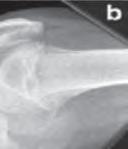

Podział złamań kości rosnących, tzw. złamań nasadowych: A – schematyczne przedstawienie klasyfikacji złamań; B – SH I (RTG, widok z przodu i z boku); C – SH II (RTG, widok z przodu i z boku); D – SH II (TK, widok z boku); E – SH III (RTG, widok z przodu i z boku); F – SH IV (RTG, widok z przodu i z boku); G – SH V (RTG, widok z przodu i z boku).

Dalszy podział jest specyficzny wyłącznie dla kości rosnących i dotyczy tzw. złamań nasadowych. Został opublikowany przez Saltera i Harrisa i jest to najważniejszy podział złamań kości rosnących (ryc. 6.3 A–G).